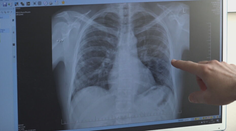

Vizionári Pacientov s rakovinou pľúc pribúda, pľúcny skríning ich má zachytiť v skorších štádiách TVNOVINY.sk 19. 11. 2024

Zdravotníctvo Blížime sa k dôležitej zmene. Rakovinu pľúc zväčša pacientom odhalia až v pokročilom štádiu Chantal R. Staruch 9. 12. 2023